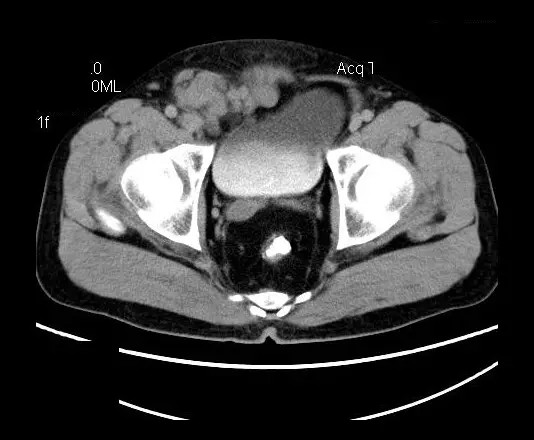

男,50岁,发现盆腔包块一月,无明显触痛,不伴发热。

【影像表现】

盆腔右前侧及邻近腹股沟区可见多发大小不等的聚集生长的结节影,病灶呈软组织密度,边缘尚规整,分界尚清,增强扫描可见不均匀强化。膀胱局部受压,盆腔未见明显肿大淋巴结影。

“盆腔”多发性神经鞘瘤

盆腔神经鞘瘤的影像学表现主要取决于肿瘤本身细胞不同组成分布及排列(Antoni A区与B区不同比例)及肿瘤是否发生退变所致。Antoni A 区由密集的梭行细胞构成,细胞核排列为栅栏状或漩涡状。Antoni B区瘤细胞稀疏,网状排列,基质含水量高,常发生囊变或出血。

平扫影像表现:Antoni A区较多病灶,在CT上呈等或略高密度影,T1WI等信号、T2WI略高信号,AntoniB区较多病灶,CT多为水样低密度、T1WI低信号、T2WI明显高信号。

增强影像表现:神经鞘膜肿瘤增强后,由于Antoni A区与B区以不同比例混合而强化不一,呈不均匀斑片状,条状强化。Antoni A 区富血供,中等或明显强化,Antoni B区乏血供,强化多不明显。